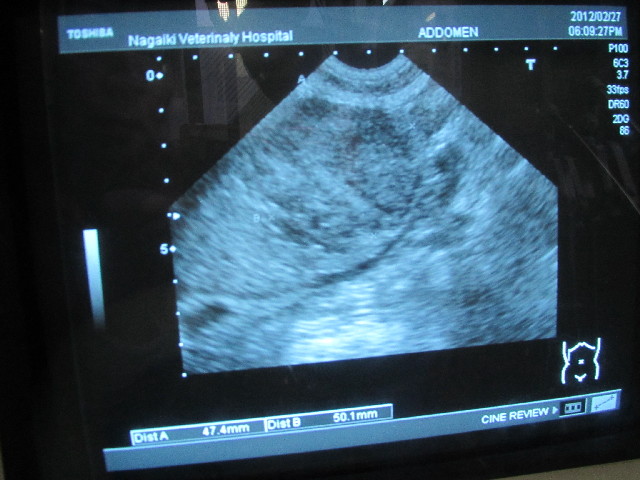

【エコー】

今日のエコーは、べべの右の腎臓に腫瘍があるのを発見したN先生です。

べべちゃんの右の腎臓の移行上皮癌の大きさは

1ケ月前は最大直径が47mmだったのが、今日は52mm。

(発見時の2011.9.26は3×3.5cmくらいですでに腎臓の25%を占めていた)

1ケ月で直径が5mm大きくなるとすると、半年後には77mm?になっちゃうのかな?

すごい大きいよね.....。

実は今回、1年前のCT画像を再度よーく院長が見直してくれたら、腎臓にはすでに腫瘍があったのがわかりました。

1年以上で最大直径が52mmになったということです。